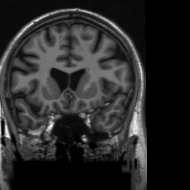

In addition, we provide the visualization results of some selected MR images reconstructed by the state-of-the-art ISTA-Net+ [33] and our proposed ResGD-Net on compressive sensing (CS) ratio 10%percent1010\%, 20%percent2020\% and 30%percent3030\%. The results are evaluated under metrics the Peak Signal-to-Noise Ratio (PSNR), the Structural Similarity (SSIM) and the Mean Squared Error (MSE). For better visualization, we rescale the pixel value by multiplying 8.0×8.0\times on the error maps (the second row of Figs. 5 - 7) when displaying.

Figure 5: Reconstruction results of a brain MR image [3] with radial mask of CS ratio 10% using the state-of-the-art ISTA-Net+ [33] and the proposed ResGD-Net. The figures in the second row are the difference images compared to the true image

Refer to caption

(a) ISTA-Net+

PSNR: 31.5131.5131.51dB

SSIM: 0.94520.94520.9452

MSE: 7.069e47.069𝑒47.069e-4

(b) ResGD-Net

PSNR: 35.6835.6835.68dB

SSIM: 0.95950.95950.9595

MSE: 2.693e42.693𝑒42.693e-4

(c) True

Figure 6: Reconstruction results of a brain MR image [3] with radial mask of CS ratio 20% using the state-of-the-art ISTA-Net+ [33] and the proposed ResGD-Net. The figures in the second row are the difference images compared to the true image